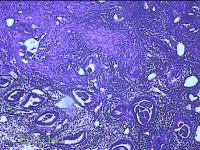

性别

女

年龄

46岁

临床诊断

异常子宫出血

一般病史

经净后阴道流血2天。

标本名称

宫腔赘生物

大体所见

灰白粉红色不规则肿物1.3x1.2x0.3cm一堆,表面光滑。

图1